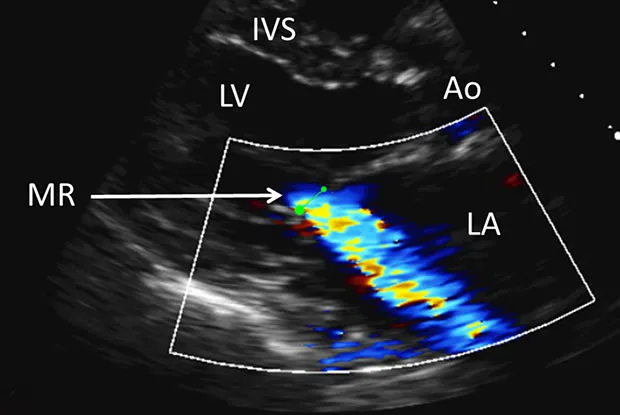

Mitral Regurgitation - Floppy Valve Fiasco

- Patho: LV → LA systolic backflow. Causes: MVP (floppy valve), RHD, IE, papillary muscle rupture, LV dilatation.

- Signs: Pansystolic murmur (apex → axilla), S3, hyperdynamic apex.

- Dx: Echo confirms. ECG: LAE, LVH. CXR: cardiomegaly.

⭐ Giant V waves in LA pressure tracing are characteristic of severe MR.